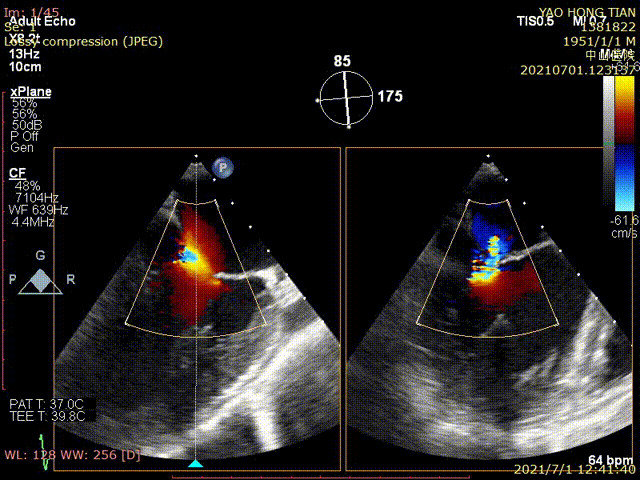

患者的術(shù)前影像

患者的術(shù)后影像